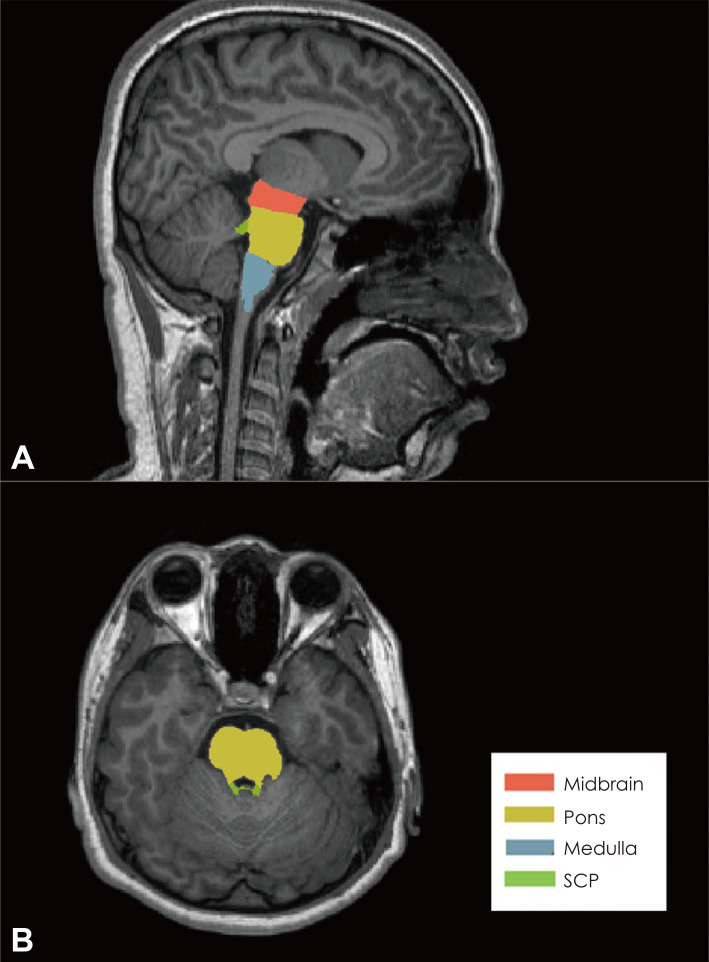

Methods: A total of 87 Korean adolescents participated in this study. The PSU group (n=20, age=16.2±1.1, female:male=12:8) was designated if participants reported a total Smartphone Addiction Proneness Scale (SAPS) score of ≥42, whereas the remaining participants were assigned to the control group (n=67, age=15.3±1.7, female:male=19:48). High-resolution T1 magnetic resonance imaging was performed, and the volume of each of the four brainstem substructures [midbrain, pons, medulla, and superior cerebellar peduncle (SCP)] was measured. Analysis of covariance was conducted to reveal group differences after adjusting for effects of age, gender, whole brain-stem volume, depressive symptoms, and impulsivity.

Results: The PSU group showed a significantly smaller volume of the SCP than the control group (F=8.273, p=0.005). The volume of the SCP and the SAPS score were negatively correlated (Pearson's r=-0.218, p=0.047).